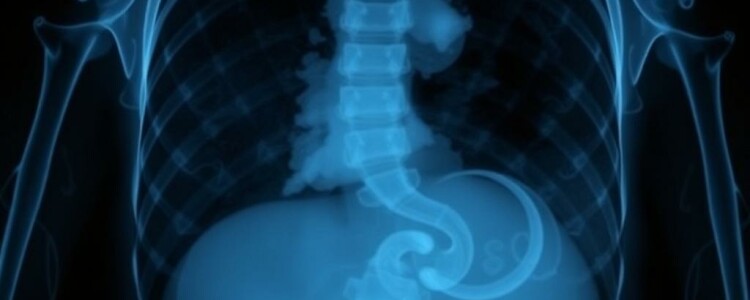

| Aire libre subdiafragmático | Perforación de víscera hueca | Alta (si se ve) | Se busca mejor en radiografía de tórax erguida o en abdomen en bipedestación; si no se detecta, no excluye perforación pequeña. |

| Rigler o doble pared | Aire libre en cavidad peritoneal (se visualizan ambos contornos de la pared intestinal) | Moderada-Alta | Requiere suficiente cantidad de aire libre; no aparece en perforaciones mínimas. |

- Sospecha de perforación con aire libre en pacientes que pueden ponerse de pie: una placa de tórax en bipedestación o una radiografía abdominal erguida detecta aire subdiafragmático con alta especificidad si es visible.

- Solicitar proyecciones adicionales si la clínica sugiere perforación y la proyección supina es normal: una placa erecta de tórax o abdomen puede revelar aire libre que no se aprecia en supino.